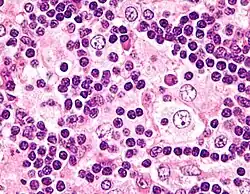

Emperipolesis

Emperipolesis is the presence of an intact cell within the cytoplasm of another cell.[1] It is derived from Greek (en is inside, peripoleomai is go round).[2] Emperipolesis is an uncommon biological process, and can be physiological or pathological.[3]

Emperipolesis is unlike phagocytosis, in which the engulfed cell is killed by the lysosomal enzymes of the macrophage. Instead, the engulfed cell remains viable within the other, and can exit at any time without causing structural or functional abnormalities in either cell.[3]

Classification

Emperipolesis has been classified into two categories:[3]

- Engulfment of hemapoietic cells by megakaryocytes such as in hematolymphoid disorders (Hodgkin's disease, leukemia, acute and chronic myeloid leukemia, non-Hodgkin's lymphoma, myeloproliferative disorders, myelodysplastic syndrome)

- Engulfment of inflammatory cells by histiocytes, which is a hallmark of Rosai-Dorfman disease[5]